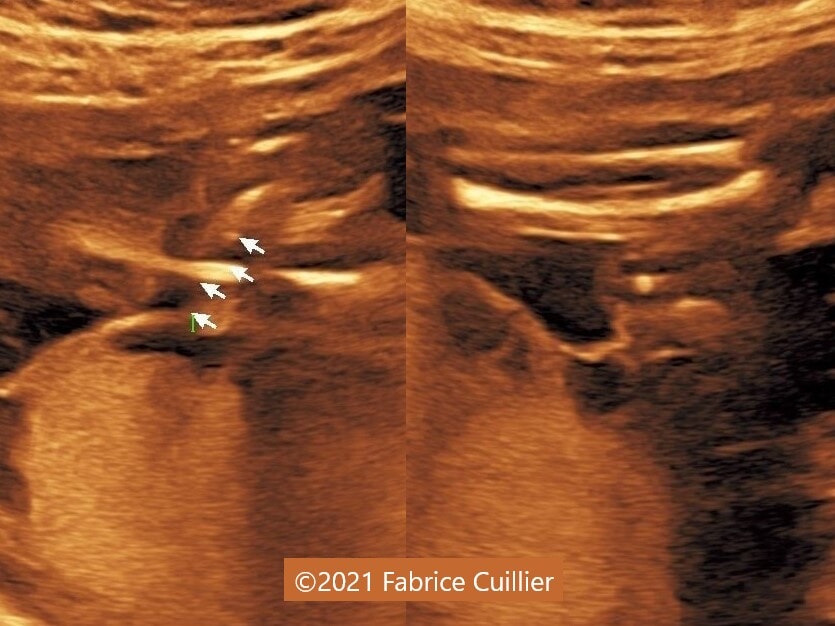

• Images 2-4: Ultrasound at 22 weeks gestation showing left foot edema with narrowing and stricture of the soft tissue due to an amniotic band (marked as ? on image 2).

• Images 5-7, video 1: Ultrasound at 23 weeks gestation showing similar finding to images 2-4.

We considered fetal surgery to release the amniotic bands and alleviate the strictured tissues, however at 24 weeks gestation there was fetal demise. External examination of the fetus confirmed the left foot edema and stricture of the left leg soft tissue. Additionally, there was amputation of several fingers of the right hand that was missed on prenatal ultrasound (Image 4).